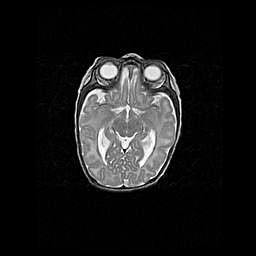

Множественные кисты обоих полушарий головного мозга, наибольшая из них в правой затылочной области. Ассиметричная атрофическая гидроцефалия.

Возраст: 7 месяцев

Вес: 5660 г

Пол: мужской

Окружность головы: 41,5 см

Срок гестации: 28-29 недель

Кисты головного мозга развиваются в результате многоочаговых некрозов вещества мозга и возникают вследствие перенесенной перинатальной инфекции, менингитов, энцефалитов, асфиксии, родовой травмы, расстройств мозгового кровообращения различного генеза. Образованию кист в веществе головного мозга плодов и новорожденных способствуют такие факторы, как высокое содержание в нем воды, недостаточная (или отсутствие) миелинизация и слабая астроглиальная реакция на повреждение.

Кисты могут сочетаться с гидроцефалией и другими поражениями головного мозга.